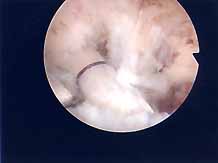

第2段階軟骨形成術

軟骨の剥離や亀裂が①より少し進んだ段階です。放っておくとさらに軟骨欠損が進み軟骨障害は広くなり且つ深くなります。この段階ではまだドリリングなどの操作は不要です。第3段階軟骨障害との間は幅広く関節鏡で見てみないと最終的に判断できません。この段階では手術結果は比較的よく平均75~90点ほどになります。